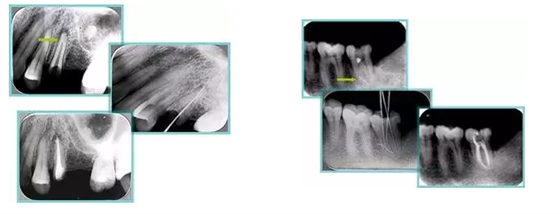

共有 4 張 X 線片,分別是術(shù)前、診斷絲 、主牙膠尖確認(rèn)、術(shù)后。

( 1 )術(shù)前:術(shù)前 X 線片用來了解牙齒的大概情況。術(shù)前預(yù)期為多根牙時(shí) X 線片應(yīng)偏頭拍攝。

( 2 )診斷絲:根據(jù)術(shù)前 X 線片進(jìn)行開髓、根管的初步預(yù)備后,需要插入診斷絲,用來指示工作器械位置。常用 10 號(hào)或 15 號(hào)擴(kuò)大器作為診斷絲插入牙髓腔。

( 3 )主牙膠尖確認(rèn):通過術(shù)前預(yù)期和診斷絲診斷,明確工作長(zhǎng)度、牙根走向,進(jìn)行根管預(yù)備。之后應(yīng)進(jìn)行主牙膠尖(中銼)確認(rèn),已明確根管是否適合充填。

( 4 )術(shù)后:觀察治療效果。